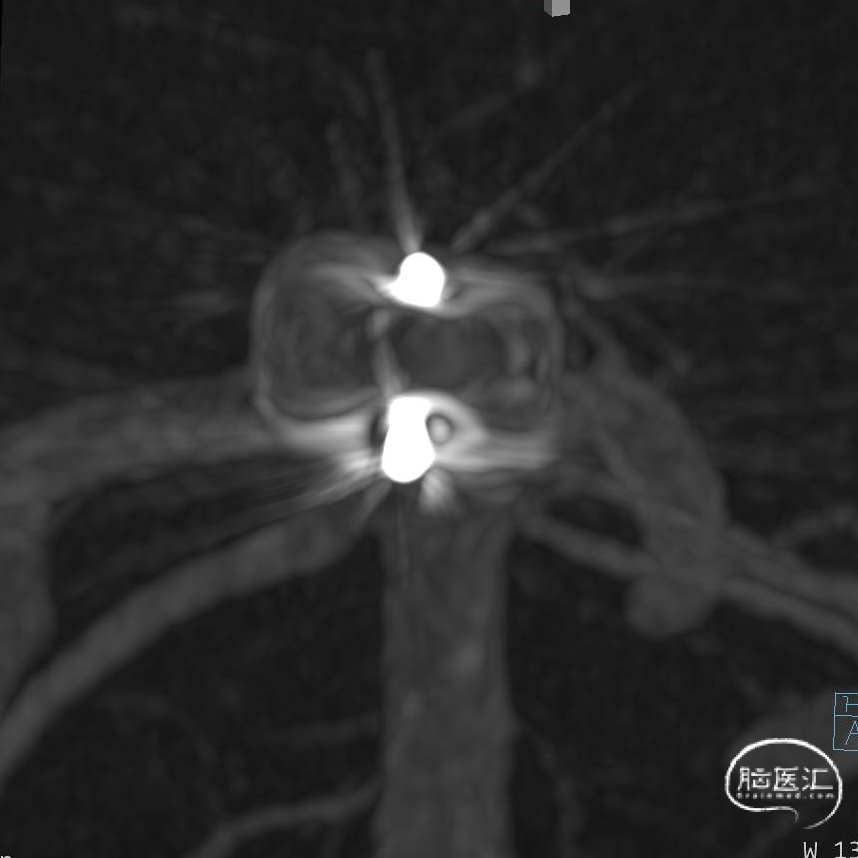

经测量可得动脉瘤宽度平均值为7.0mm,动脉瘤高度为5.18mm,选用WEB™ SL 8*4。

WEB™经由VIA™微导管送入动脉瘤瘤腔并完全释放。术后即刻造影显示WEB™尺寸合适,贴壁良好,分支等血流通畅。解脱后再次造影,可见动脉瘤瘤腔内有明显造影剂滞留。